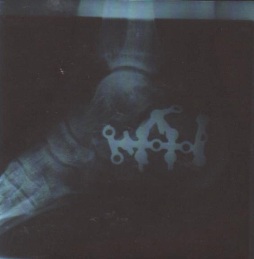

Six semaines sont passées. Je m'affranchis, tout en prenant toutes précautions pour ne pas heurter ce pied encore très sensible et infirme. Le mollet a fondu. A mon premier rendez-vous à l'hôpital, le chirurgien me confirmera que la marche, c'est pour plus tard. Et je verrai à la radiographie l'étrange attirail installé au creux de mon pied. Un meccano, une surprise, une inquiétude ! Et alors !